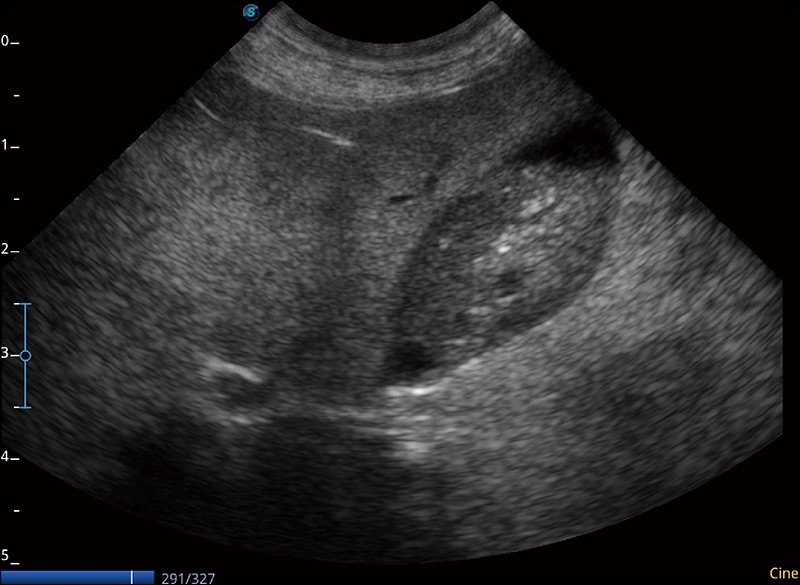

α1卓越的图像质量和便捷的工作流程,使每位宠物医生都能轻松扫查。其全面的兽用应用功能和紧凑型的结构设计,可以满足动物检查的多种需要。专业的预设检查模式和多领域测量软件包有助于为不同类型的动物提供检查, 让宠物医生能够出色的完成工作。

实时宽景成像

可实时观察感兴趣区域和病变位置